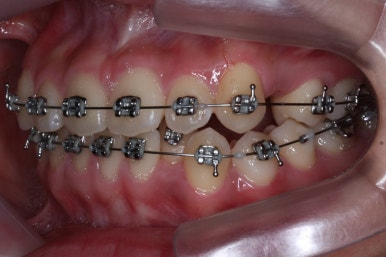

우선 위쪽 작은 어금니 부터 발치하였습니다.

송곳니 바로 뒤쪽의 작은 어금니를 뽑은 것을 보실 수 있겠습니다.

이제는 아래쪽 작은 어금니도 뽑았습니다.

교정치료를 시작한지 3개월 밖에 지나지 않았을 시점인데도 벌써 덧니가 많이 가지런해졌습니다. 치아는 자리만 확보되면 쉽게 가지런해질 수 있습니다.

가지런해지지 않았던 아래 앞니 하나도 금새 가지런해졌습니다.